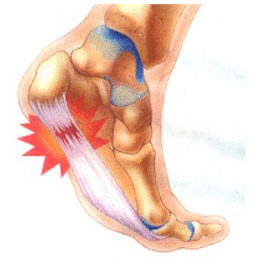

La temida fascitis plantar cuando se cronifica en el tiempo pasa a denominarse fasciosis ambas son patologías musculo-ligamentosas que aparecen en la planta del pie y llegan a ser incapacitantes (el dolor suele darse en el momento del despegue en la marcha y/o carrera). Estas patologías pueden ser debidas y/o estar presentes a la vez que el espolón calcáneo (osificación anómala en el talón). En éste caso el dolor por espolón calcáneo se da con el primer paso, al choque de talón con el suelo.

- Espolón Calcáneo

- Infiltración en zona espolón

- Infiltración en Fascia Plantar